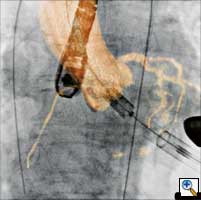

Figure

Figure 6. Deployment of an Edwards SAPIEN valve with 3D guidance.

3D images are acquired at the start of the procedure with the patient lying on the OR table within 5 seconds. After reconstruction and segmentation (necessary time 2 minutes) the 3D volume of the aortic valve and ascending aorta serves for precise sizing of the aortic annulus and planning for the best projection perpendicular to the aortic annulus. The volume is then overlaid over the live 2D fluoroscopy images and supports precise placement of the aortic valve under rapid pacing. Courtesy of Heart Center Leipzig

CT-like 3D imaging with the angiography system